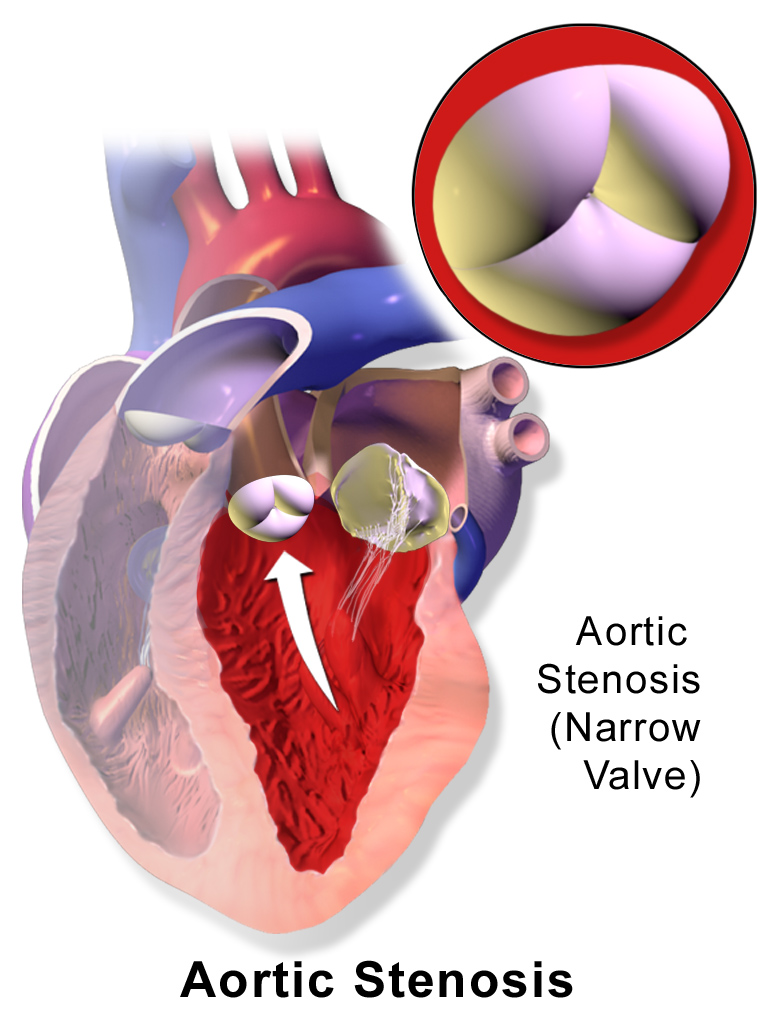

Aortic Stenosis

Aortic stenosis occurs when the aortic valve orifice narrows.

Aortic stenosis is typically brought on by fibrosis and calcification from wear and tear.

Aortic stenosis causes a crescendo-decrescendo murmur after a systolic ejection click.

Complications of aortic stenosis include:

- Concentric left ventricular hypertrophy

- Angina

- Syncope

- Cardiac failure

- Microangiopathic hemolytic anemia

Treatment of aortic stenosis is valve replacement.